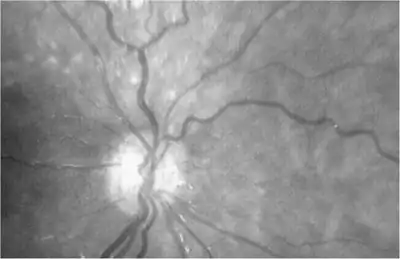

![]() | |

| The optic nerve is underdeveloped in this condition | |